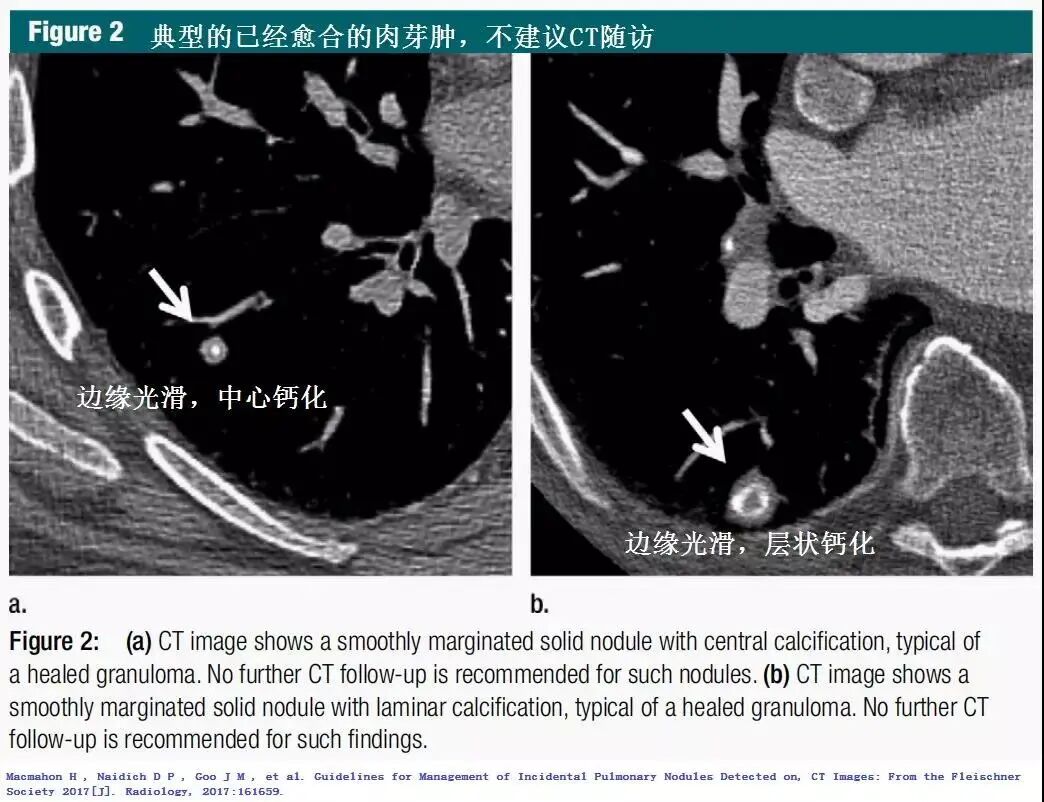

胸部CT在体检中的应用越来越普遍,很多人在做完CT后被告知:肺上长了结节。 其实体检被检测出的肺结节只有5%是恶性的。 我们一直在跟大家强调肺结节问题,尽管这样还是有很多患者不放心,担心的睡不着觉。 那什么样的肺结节该切?什么样的不该切呢? 有一点要明确肺结节不等于肺癌,它在人体内出现的原因大致分为三种:炎性疾病、先天性疾病和肿瘤。 它并不是一个具体的疾病名称,它跟咳嗽一样是一种表现,感冒发烧会咳嗽,肺炎了也会咳嗽。肺结节就是指在影像检查上看到的直径≤3cm、类圆形的、密度增高的实质性或亚实质性的肺部阴影。 首先给大家看看哪些是良性的(来自Fleischner协会指南的经典CT) CT影像判断肺结节的良恶性主要是从结节大小、形态、密度等特征来进行判断(注意:临床上具体需由专业医生综合分析判断,切勿自行臆断)。 1.结节大小:随着肺结节体积增大,其恶性概率也随之增加。但肺结节大小的变化对其定性诊断价值有限,还需密切结合形态及密度的改变; 2.结节外形:良性肺结节边缘清晰、光滑;恶性肺结节有分叶、空泡、毛刺、血管聚集、胸膜凹陷的特点; 3.结节密度:部分实性结节的恶性概率最高,其次是磨玻璃结节和实性结节。 CT图是诊断的第一步,要诊断结节情况需要结合其他相关检查,如结核菌素试验是否阳性,肿瘤标志物情况等。具体检查需要做哪些?不要慌,找专科医生并信任他。